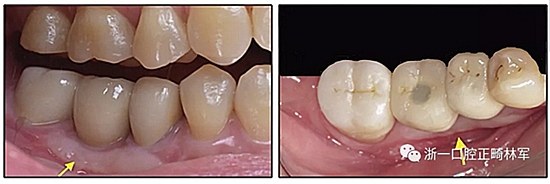

圖18. A,在術(shù)前,稍靠前的角度現(xiàn)實,種植體支持修復(fù)體的遠中面凹陷最明顯(中心); B,從下頜右側(cè)第二前磨牙至第二磨牙附著齦的頂部作水平切口,翻出部分厚皮瓣; C,從右側(cè)腭粘膜獲得1個5×15-mm游離齦瓣; D,供體部位覆蓋富含血小板的纖維蛋白以增強傷口愈合并用5-0尼龍線交叉縫合; E,用5-0尼龍線將游離齦瓣縫合到受體部位; F,放置Coe-Pak敷料以保護皮瓣并防止頰側(cè)皮瓣與游離皮瓣競爭附著到受體組織的下部。

圖19. 在術(shù)后愈合期后,游離齦瓣增加了附著組織的寬度(左箭頭),并矯正了咀嚼時食物向頰側(cè)的問題(右箭頭)